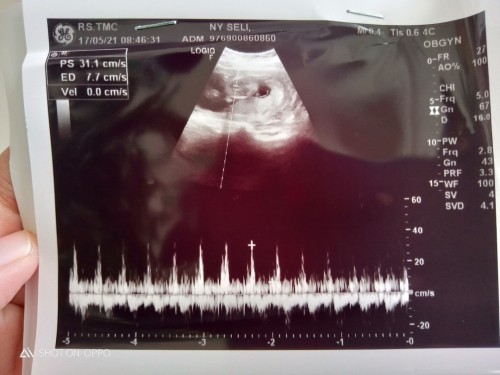

Hallo bunda.. Mau tanya, saya tadi usg,usia kehamilan 14minggu mau ke 15, placenta di bawah, bahaya kah ? Apa bisa bergeser keatas ? Tdi sya cuma nanya apakah bisa d prbaiki biar ke atas,ktnya ga bisa hrus dgn sndiri nya..gitu bun Trus,kalo berhubungan intim itu boleh ga pada saat sekarang(placenta dibawah ?) Sharing aja ya bun.. Terimakasih 🙏 #seriusnanya #bantusharing